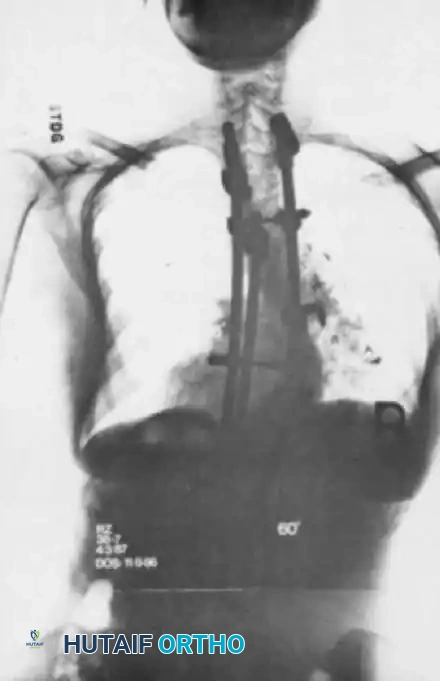

Fig. 41-15 Postoperative AP radiograph demonstrating a long posterior spinal fusion construct utilizing high-density pedicle screw fixation to correct a severe coronal deformity.